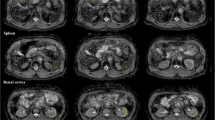

The maximum RMS was 17.1 mm and was observed in a clavicular lesion in the Thorax Station. In the Abdomen and Pelvis Station, the maximum RMS values were 14.6 mm and 15.1 mm, respectively. Across all lesions, the average RMS was 6.0 mm (95% CI 5.0–7.2). When grouped by station, the mean RMS for Thorax, Abdomen, and Pelvis Stations were 8.2 mm (95% CI 6.6–10.6), 6.5 mm (95% CI 4.3–8.5), and 4.1 mm (95% CI 2.7–5.9), respectively. Examples of vertebral and femoral lesions are displayed in Fig. 4. The distributions of RMS values are illustrated in Fig. 5. RMS values did not significantly differ when using bounding boxes with edges at 7 or 12 voxels away from the lesion edges.

Examples of bone metastases as seen on b = 0 s/mm2 DWI pre-and post-DisCo. The top row (A–D) shows a vertebral lesion in the Thorax Station. The bottom row (E–H) shows a lesion within the left femoral head in the Pelvis Station. (A,E) T2-weighted images at the corresponding level with an orange bounding box drawn around the lesion. (B,F) T2-weighted images zoomed in to visualize lesion and surrounding area. (C,G) Zoomed in DWI b = 2000 s/mm2 and b = 0 s/mm2 images before DisCo, respectively. (D,H) Zoomed in DWI b = 2000 s/mm2 and b = 0 s/mm2 images after DisCo, respectively. Outlines of the lesion annotations are overlaid in red. In both examples, the lesions were translated anteriorly following DisCo. Without DisCo, lesion localization may have erred posteriorly. DisCo distortion correction.

Distribution of RMS of distortion and MI between b = 0 s/mm2 and T2-weighted images. (A) Distortion for lesions across all stations (black) as well as the distribution within specific imaging Stations (red, blue, and yellow). Distortion was estimated by calculating the RMS of the values in the distortion map that correspond to the lesion annotation and immediately surrounding areas (see Eq. (1)). (B) Change in MI values between the DWI b = 0 s/mm2 and T2-weighted images after DisCo. A value larger than 0 indicates improved agreement between DWI b = 0 s/mm2 and T2-weighted images. Again, we plot the distribution for all lesions as well as the breakdown for different Stations. (C) For illustrative purposes, we categorized lesions into three distinct anatomic groups: Vertebra, Pelvis, and Other. The Other category represents lesions in bones such as the clavicle, sternum, and femur. The distribution for distortions for each anatomic group is plotted. (D) Change in MI values between the DWI b = 0 s/mm2 and T2-weighted images after DisCo broken down by anatomic group. DisCo led to consistent increases in similarity between DWI b = 0 s/mm2 and T2-weighted images. RMS root mean square, MI mutual information.

To explore the extent to which B0 inhomogeneity may induce geometric distortions, we plotted example lesions from different parts of the skeleton and in different imaging stations (Figs. 2, 4). The metastasis in the left femoral head shown in Fig. 4E–H, for example, underwent B0 inhomogeneity-induced contraction, as can be appreciated with the dark strip of voxels at the anterior edge of the lesion in Fig. 4G. Additionally, the right clavicular lesion included in Fig. 2 became more globular in shape and was partially rotated after application of DisCo.